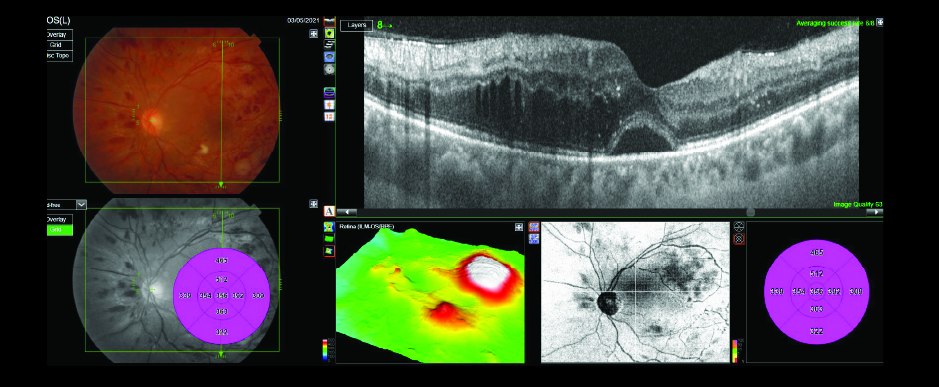

Case Study – Advanced PDR with Non-Perfusion and Macular Edema

33-year-old Caucasian female with history of myopia, vulvar cancer, family history of diabetes and liver cancer presented with a visual acuity of 20/200 (OD), 20/50 (OS). Intraocular pressures were measured 17mmHg (OD), 19mmHg (OS). A posterior subcapsular cataract was observed with all other ocular physiological characteristics normal.

3D Wide OCT Combination Scans, fluorescein angiography and fundus photos were obtained OU. Macular edema, subretinal fluid, intraretinal hemorrhages, cotton wool spots (CWS), nonperfusionable vessels and hemorrhages in the peripheral vessels were visualized OU.

Diagnosis: Advanced Proliferative Diabetic Retinopathy (PDR), retinal non-perfusion and macular edema OU

Treatment: Bevacizumab, PRP laser (OU)

Discussion: 45-degree fluorescein images, true-color photos of the retina and penetrating swept-source OCT scans helped to confirm and document the clinical findings